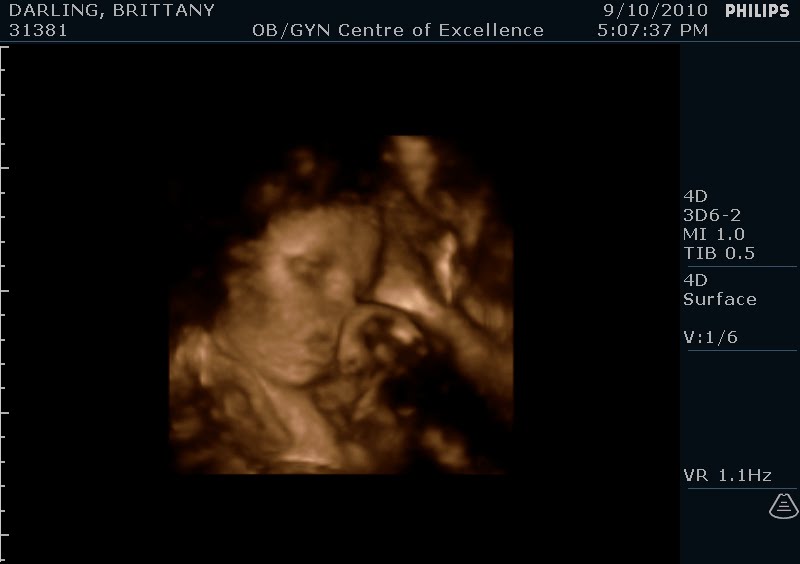

4-D ultrasound pics!

Hi....we had a 4-D ultrasound done on 9.10.10 and here are the pics from it! I was almost 33 weeks when we had this done. It's so amazing that we can see so much detail! I can't wait to meet baby Will to see if these are accurate! He really likes sucking on his hands already, and I think his cheeks look a little chubby...how cute! I'm a little biased :)